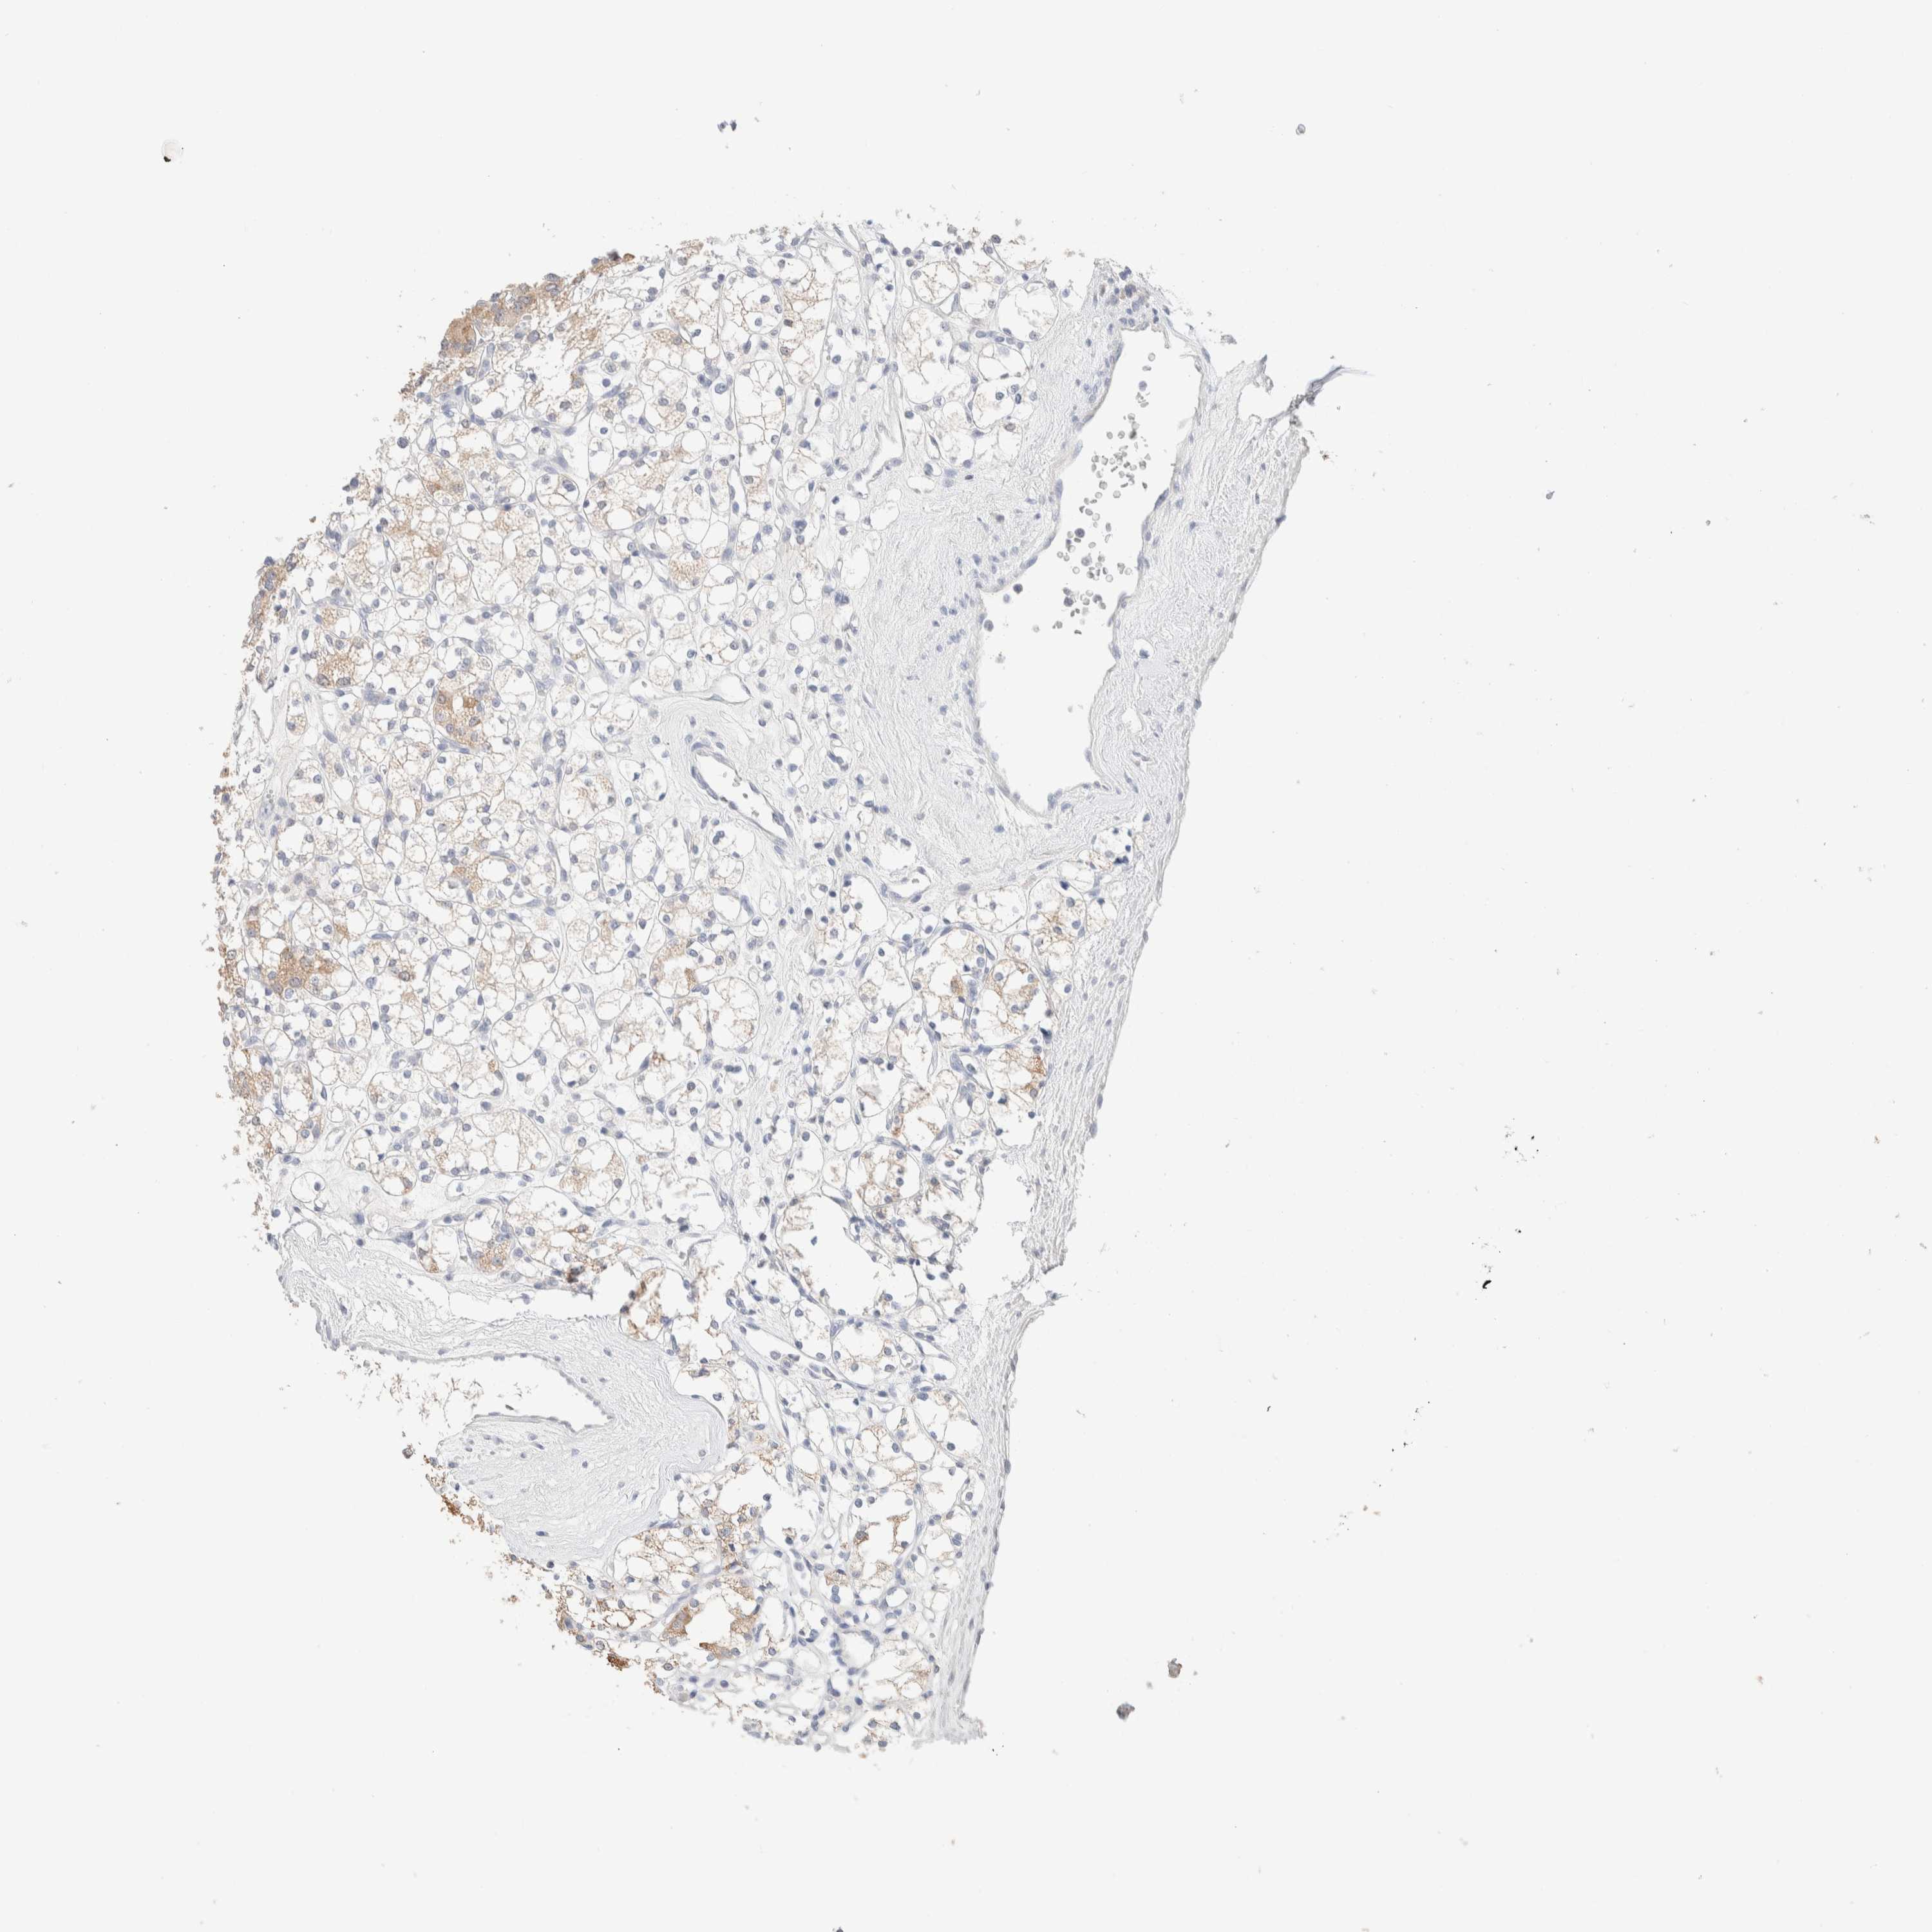

KIDNEY RENAL CLEAR CELL CARCINOMA (TCGA) - Interactive survival scatter ploti

The Survival Scatter plot shows the clinical status (i.e. dead or alive) for all individuals in the patient cohort, based on the same data that underlies the corresponding Kaplan-Meier plots. Patients that are alive at last time for follow-up are shown in blue and patients who have died during the study are shown in red.

The x-axis shows the expression levels (FPKM) of the investigated gene in the tumor tissue at the time of diagnosis. The y-axis shows the follow-up time after diagnosis (years). Both axes are complimented with kernel density curves demonstrating the data density over the axes. The top density plot shows the expression levels (FPKM) distribution among dead (red) and alive patients (blue). The right density plot shows the data density of the survived years of dead patients with high and low expression levels respectively, stratified using the cutoff indicated by the vertical dashed line through the Survival Scatter plot. This cutoff is automatically defined based on the FPKM cutoff that minimizes the p-score. The cutoff can be changed by dragging the vertical line or by entering a cutoff value in the square labeled "Current cut-off".

Under the Survival Scatter plot the p-score landscape (black curve; left axis) is shown together with dead median separation (red curve; right axis). Dead median separation is the difference in median mRNA expression between patients who have died with high and low expression, respectively. It is calculated as follows: median FPKM expression of dead patients with high expression - median FPKM expression of dead patients with low expression. This is intended to aid the user in visually exploring custom cutoffs and the associated p-scores and dead median separation.

Individual patient data is displayed and can be filtered by clicking on one or more of the category buttons on the top of the page. Categories describing expression level and patient information include: high, low, alive, dead, female, male and tumor stages. The scale of the x-axis can be toggled between linear and log-scale by clicking on the "x log" button. Mouse-over function shows TCGA ID, patient information and mRNA expression (FPKM) for each patient.

& Survival analysisi

Kaplan-Meier plots summarize results from analysis of correlation between mRNA expression level and patient survival. Patients were divided based on level of expression into one of the two groups "low" (under cut off) or "high" (over cut off). X-axis shows time for survival (years) and y-axis shows the probability of survival, where 1.0 corresponds to 100 percent.

RIDA is potential prognostic, high expression is favorable in Kidney Renal Clear Cell Carcinoma (TCGA)

: 67.63

Average pTPM 116.6

Number of samples 521